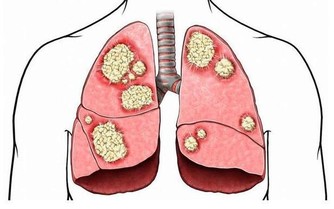

肝癌一般是進行性加重,主要是肝癌腫瘤不斷增大壓迫肝包膜所致。